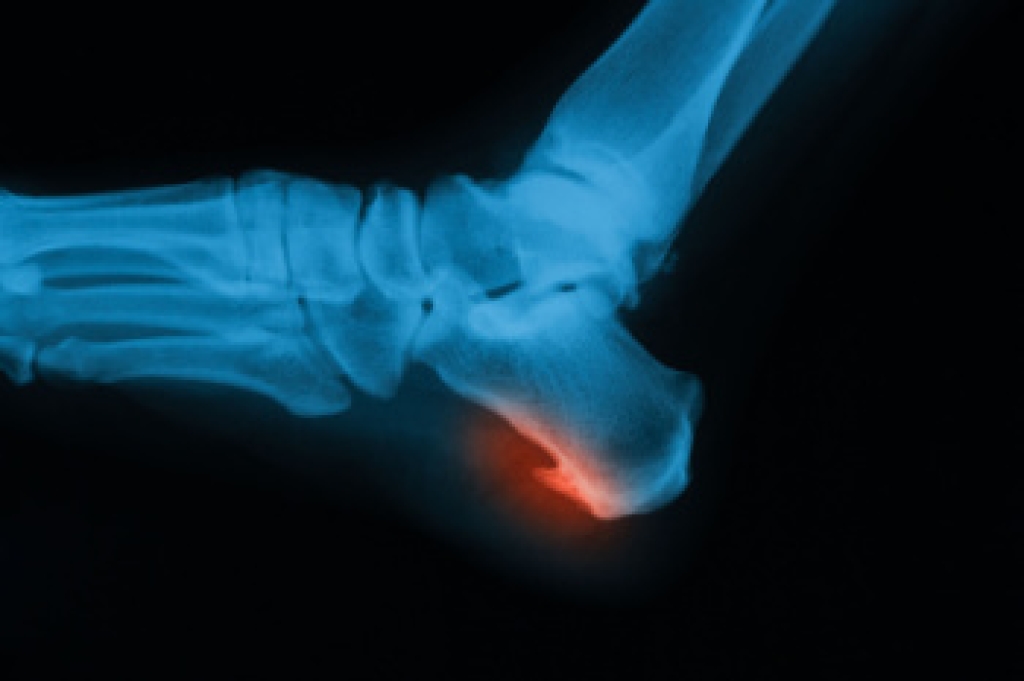

Heel spurs are bony growths that can form on the underside of the heel bone, often associated with plantar fasciitis. These spurs develop over time as a result of repetitive stress or tension on the foot. The primary cause is the strain placed on the plantar fascia, a thick band of tissue that connects the heel to the toes. As this tissue is repeatedly stretched or stressed, calcium deposits may accumulate, leading to the formation of a heel spur. Common symptoms include sharp pain in the heel, particularly when walking or standing after rest. Swelling and tenderness surrounding the heel area may also occur. Although heel spurs are often painless, they can cause significant discomfort and restrict normal movement if left untreated. If you have heel pain, it is suggested that you contact a podiatrist who can accurately diagnose a heel spur, and offer appropriate relief and treatment solutions.

Heel spurs are formed by calcium deposits on the back of the foot where the heel is. This can also be caused by small fragments of bone breaking off one section of the foot, attaching onto the back of the foot. Heel spurs can also be bone growth on the back of the foot and may grow in the direction of the arch of the foot.